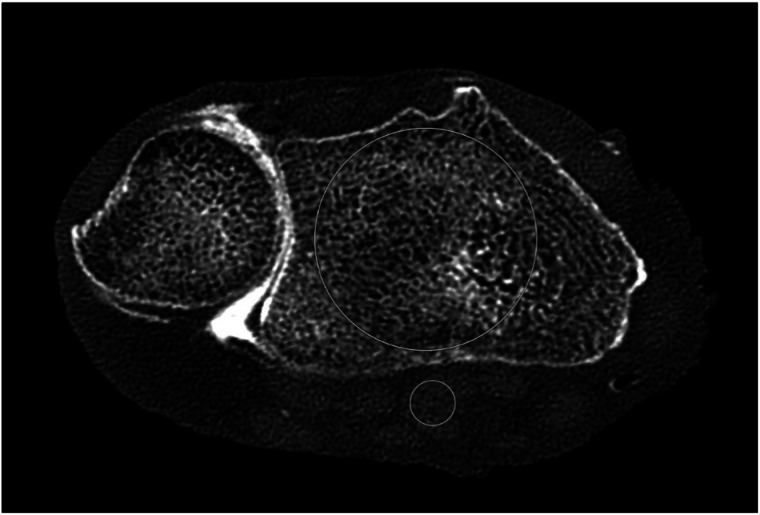

Background: This study aimed to evaluate the imaging performance and diagnostic value of a photon-counting detector (PCD) computed tomography (CT) compared to an energy-integrating detector (EID) and flat panel detector (FPD) for cadaveric wrist arthrographies.

Methods: Following ethics committee approval, ten cadaveric wrists were injected with diluted iodinated contrast agent. CT arthrographies using PCD-, EID-, and FPD-CT were performed. Six dose protocols between 0.1 mGy (using a tin filter) and 6 mGy, ultrahigh-resolution-mode, and two reconstruction kernels were used for the PCD-CT and EID-CT. FPD-CT images were reconstructed using a "normal" and "sharp" kernel. Signal-to-noise ratios (SNR) and contrast-to-noise ratios (CNR) were calculated and analyzed using analysis of variance (ANOVA) and post hoc tests. Three blinded radiologists independently rated image quality concerning trabecular, cartilage, and intrinsic structures. Intraclass correlation coefficients (ICC) were calculated, followed by a Friedman and post hoc test.

Results: At 1.5 mGy, 3 mGy, and 6 mGy with the Br89 kernel, the PCD-CT yielded up to 2.35 times higher SNR and up to 7 times higher CNR than dose-equivalent and higher dose EID-CT scans. Subjective ratings favored the PCD-CT over the EID-CT and occasionally the FPD-CT, with a combined ICC of 0.942. Applying sharper kernels, SNR did not differ significantly between the PCD-CT (1.5 mGy, 3 mGy, and 6 mGy) and the FPD-CT.

Conclusion: Using sharp kernels, the PCD-CT provided superior image quality to the EID-CT and achieved comparable or better quality than the FPD at certain parameters. Thus, the PCD-CT could be considered a possible alternative in clinical routine for evaluating wrist injuries.